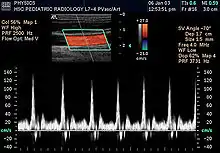

سونوگرافی داپلر

سونوگرافی داپلر (به انگلیسی: Doppler sonography) نوعی از سونوگرافی است که برای تصویربرداری خون جاری در قلب و عروق استفاده میشود. در مامایی نیز از سونوگرافی داپلر جهت گوش دادن به صدای قلب جنین استفاده میشود. سونوگرافی داپلر همچنین برای تشخیص ترومبوز وریدی، واریکوسل، تنگی و انسداد شریانی به ویژه در شریان کاروتید استفاده میشود.[2][3][4]